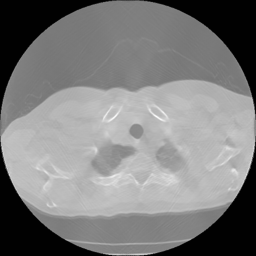

Limited angle CT reconstruction is a very challenging ill-posed issue and of great interest in several clinical applications, such as digital breast tomosynthesis [1], dental tomography [2], short exposure time [3], etc. In a limited-angle CT scan, the projection data can be obtained in less than 180superscript180180^{\circ} angular range, and the data insufficiency degrades reconstruction quality with streaking artifacts(fig 1 (a)(b)).

Figure 1: Qualitative illustration of the task: (a) given a limited-angle sinogram; (b) automatic inpainting result using our sinogram inpainting network (SIN); (c) ground truth sinogram; (d) reconstruction result of state-of-art iterative SART method with TV normalization; (e) our method output; (f) ground truth image